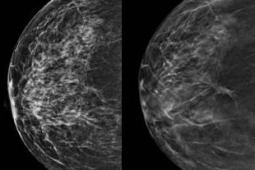

Rak piersi jest jednym z najczęstszych nowotworów u kobiet i w związku z tym prowadzony jest program badań przesiewowych (mammografia) dla pań w wieku 50-69 lat. Zwiększająca się jakość opieki medycznej powoduje, że żyjemy coraz dłużej - czy zatem ukończenie 70. roku życia powinno skłaniać do rezygnacji z mammografii? Okazuje się, że niekoniecznie.

Na corocznym spotkaniu Towarzystwa Radiologicznego Ameryki Północnej (RNSA) w dniach 25.-30. listopada zostaną zaprezentowane wyniki analizy skuteczności mammografii na ogromnej grupie aż 763 256 pacjentek. Zespół z Elizabeth Wende Breast Care w Rochester wyselekcjonował dane 76 885 pacjentek w wieku co najmniej 75 lat; średni wiek badanej subpopulacji wynosił 80,4 lat.

W sumie zdiagnozowano 645 nowotworów złośliwych u 616 pacjentek, co daje częstość występowania raka piersi w tej grupie wynoszącą 8,4 przypadków na 1000 wykonanych mammografii. Ponadto, spośród całej, kilkusettysięcznej populacji objętej screeningiem aż 16% pacjentek, u których zdiagnozowano nowotwór, stanowiły panie w wieku 75+. Naukowcy odkryli również, że 82% zdiagnozowanych zmian stanowiły nowotwory inwazyjne, z których 63% stanowiły zmiany w stopniu 2. lub 3. Aż 98% zdiagnozowanych pacjentek kwalifikowało się leczenia chirurgicznego - oczywiście celem wyleczenia. Dodatni węzeł wartowniczy odnotowano u 7% pacjentek poddanych operacji. Zaledwie 17 chorych nie było leczonych chirurgicznie z powodu zaawansowanego wieku lub złego ogólnego stanu zdrowia.

Wiemy już od dawna, że mammografia odgrywa kluczową rolę we wczesnym wykrywaniu raka piersi; wczesne wykrycie prowadzi bowiem do lepszych opcji leczenia i poprawy przeżycia. Powyższe doniesienie stanowi bardzo mocny argument za rozszerzeniem screeningu na grupę pacjentek powyżej 70. roku życia - miejmy nadzieję, że czeka nas to już niedługo.